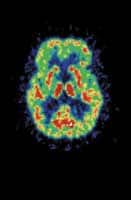

The good news is the exciting finding that the brain can generate new neurons. After decades of believing that neurons can only be lost with age, scientists at Princeton have recently demonstrated that new nerve cells are indeed being created in the brains of monkeys. The new neurons are formed deep in the brain near the ventricles, then migrate to various areas, including the prefrontal cortex, regarded as the seat of "higher cognitive functions."

The implication of this discovery is that neurons (brain cells) can at least be partly replaced. The old dogma held that the brain inevitably shrinks and progressively atrophies as we age. Now this dismal view can be discarded in favor of a new search for ways to help the brain regenerate and preserve its youthful powers.

If the synthesis of new neurons takes place in human brains as well, and everyone thinks it does, there is great hope for reversing brain damage and preserving good cognitive function well into old age. The new discovery also points to the importance of providing the brain with the right nutrients, so that the new cells can be easily formed. It would appear that neuronal regeneration is facilitated when there is an abundance of cell membrane building blocks such as phosphatidyl choline and phosphatidyl serine. Considering that nerve growth factors are under hormonal control, adequate sex-steroid hormone replacement is also an important consideration.